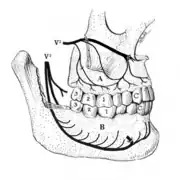

Disorders of the maxillary sinus can be referred to the upper back teeth. The posterior, middle and anterior superior alveolar nerves are all closely associated with the lining of the sinus. The bone between the floor of the maxillary sinus and the roots of the upper back teeth is very thin, and frequently the apices of these teeth disrupt the contour of the sinus floor. Consequently, acute or chronic maxillary sinusitis can be perceived as maxillary toothache,[39] and neoplasms of the sinus (such as adenoid cystic carcinoma)[40]: 390 can cause similarly perceived toothache if malignant invasion of the superior alveolar nerves occurs.[41]: 72 Classically, sinusitis pain increases upon Valsalva maneuvers or tilting the head forward.[42]